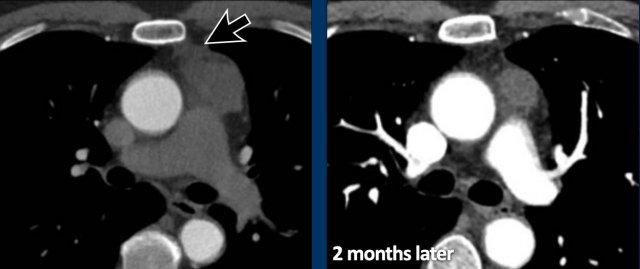

Các hình ảnh này của một bệnh nhân nam 43 tuổi có đau ngực.

Hình ảnh

Có một khối ở trung thất trước mạch máu.

Bờ không đều và tổn thương dương tính trên PET-CT.

Thảo luận

Chẩn đoán có khả năng nhất là thymoma, có thể là thể xâm lấn hoặc thậm chí là ung thư tuyến ức.

Tiếp tục xem phim chụp tiền phẫu hai tháng sau…

Hai tháng sau, một phim chụp tiền phẫu được thực hiện.

Rõ ràng là tổn thương đã nhỏ hơn.

Tuy nhiên, phẫu thuật viên vẫn quyết định cắt bỏ tổn thương và kết quả giải phẫu bệnh là ung thư tuyến ức.

Chúng tôi không có giải thích rõ ràng cho những gì đã xảy ra ở đây.

Có một số phản ứng trong mô mềm xung quanh khối u trên phim chụp đầu tiên (mũi tên).

Có thể đã có tình trạng viêm trong khối u và các mô xung quanh, khiến khối u trông lớn hơn.